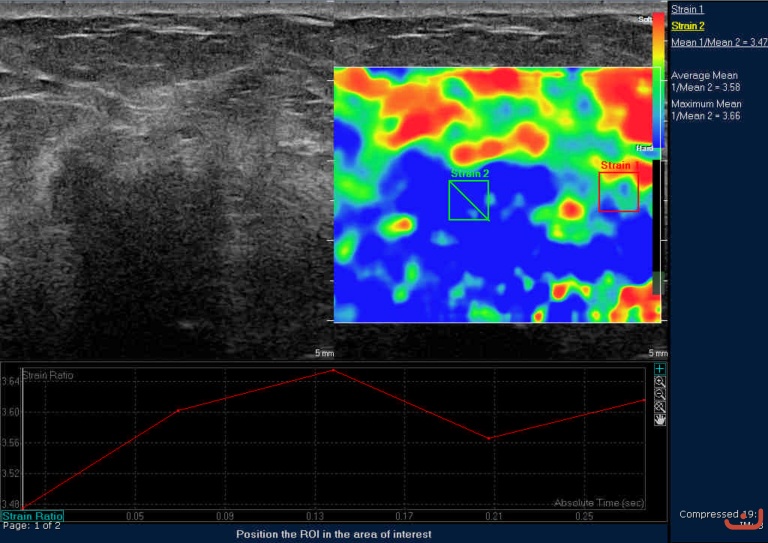

Case 40-E1

Malignant solid mass

Friday, 22 May 2015

290.74 KB (768 x 543 px)